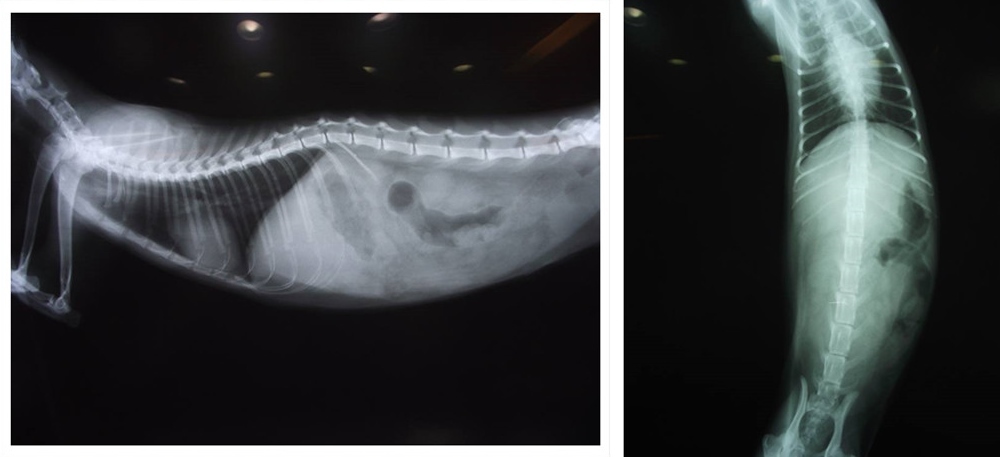

照x光時

這隻貓的左腎長軸只有2.2公分(嚴重發育不良),右腎2.9公分(中度發育不良),因為正常腎臟長軸是3.6公分以上..

並且

再加上嚴重的肺炎與泡疹病毒感冒,本來腎指數有下降到BUN79 和CRSC3.5,但因為已經七天不願進食,一直採取打點滴與灌食!